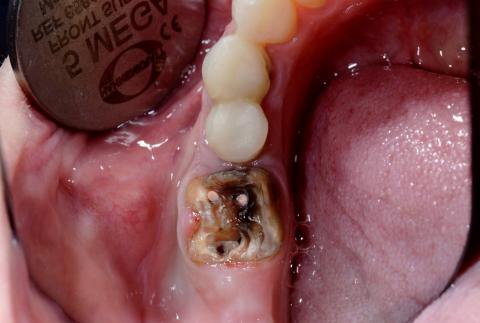

Severe Open Carious Molar With Pulp Exposure Causing Pain, Infection, and Oral Odor

Visual Examination (Zoom 100% – Clinical Findings)

Lower posterior molar (likely first or second molar)

Extensive crown destruction due to advanced dental caries

Open pulp chamber clearly visible

Dark brown to black necrotic dentin

Two exposed root canal orifices

Food debris and bacterial biofilm present

Surrounding gingiva appears inflamed

Strong likelihood of active bacterial infection